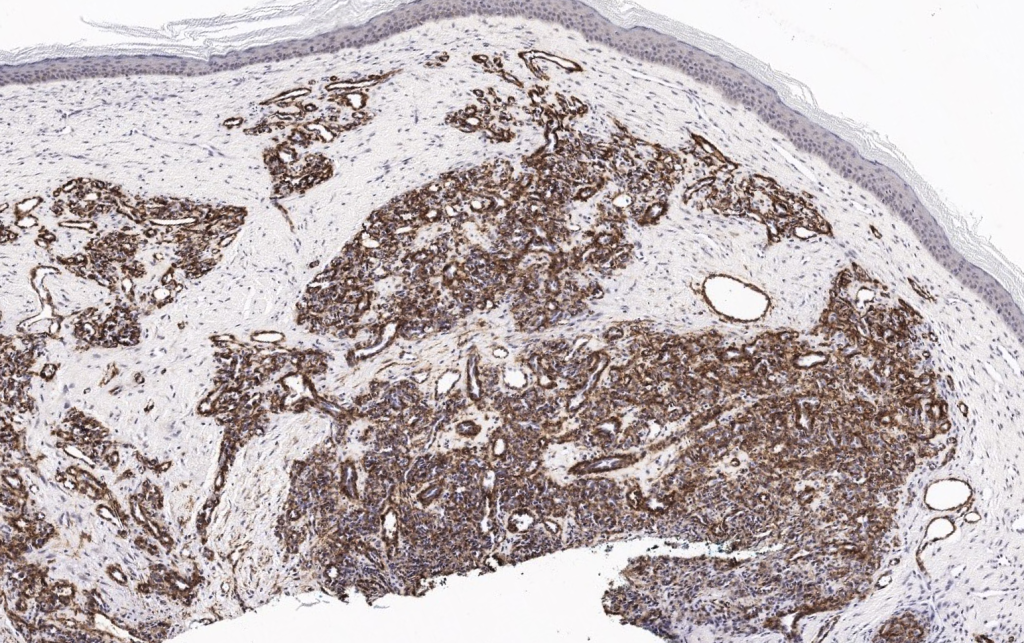

Neoplasia benigna perivascular originada en las células musculares lisas modificadas del cuerpo glómico neuromioarterial (cuerpo de Sucquet-Hoyer), estructura arteriovenosa especializada en la termorregulación digital. Se localiza típicamente en la dermis y tejido celular subcutáneo de los dedos, especialmente en la región subungueal. Samaniego 2009, Hazani 2008, Smith 2019 - Glomangioma / malformación glomovenosa (glomuvenous malformation, GVM)

- Tumor glómico sólido

- Glomangioma (tumor glómico con componente vascular prominente)

- Glomangiomioma (con mayor componente de músculo liso) Samaniego 2009, Smith 2019